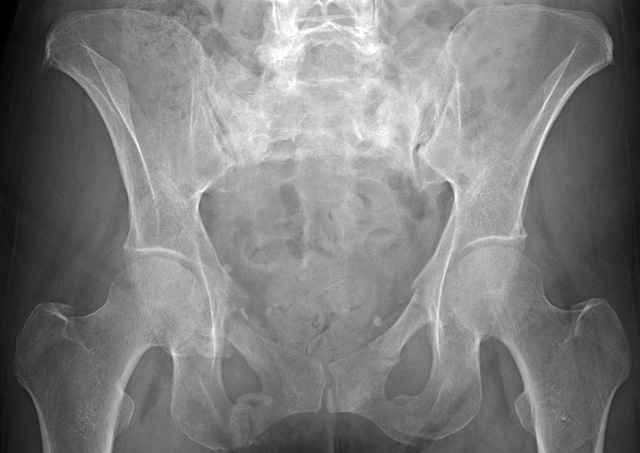

Here are a recent patient’s example slides...

54 yo Female Fell c/o Pain

3 Months After Fall

Continued Pain & Immobility

Percutaneous Fixation

(B) Ramus-Retrograde

2 TransIliac-TransSacral

Upper Segment